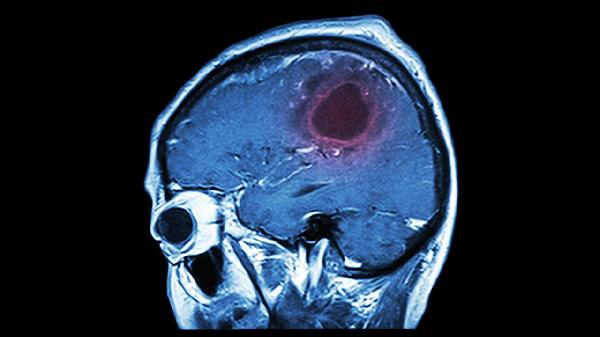

脑血栓症状主要包括肢体无力、言语不清、头晕头痛、视力障碍和意识障碍。脑血栓是由于脑血管内血栓形成导致脑组织缺血缺氧引起的,可能与动脉粥样硬化、高血压、糖尿病等因素有关,通常表现为突发性神经功能缺损。

大面积脑血栓或脑干梗死可导致嗜睡、昏迷等意识状态改变,伴随瞳孔异常、呼吸节律紊乱。这种情况提示病情危重,需紧急处理脑水肿,常用甘露醇注射液降低颅内压,配合吡拉西坦氯化钠注射液促进脑代谢,必要时进行重症监护治疗。